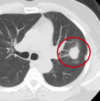

Use these for diagnosis of what?

- Radiographically presents with nodular, irregular, pleural thickening, poss pleural effusion, and pleural plaquing

- CXR

- CT

- Thoracentesis

- Surgical biopsy

- Usually necessary for diagnosis

- Difficult to diagnose

- PET

- Helpful in ?malignancy; staging; poss surgical candidate

Mesothelioma